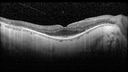

78 year old man: 20/32 OD and 20/50 OS - RP1 Gene is Bad -- > RP with Novel Amino Acid Change in GLY723Stop sequence of the RP1 gene - consistent with AD RP

Retinitis Pigmentosa - RP1 Mutation428 views78 year old man: 20/32 OD and 20/50 OS - RP1 Gene is Bad -- > RP with Novel Amino Acid Change in GLY723Stop sequence of the RP1 gene - consistent with AD RP00000